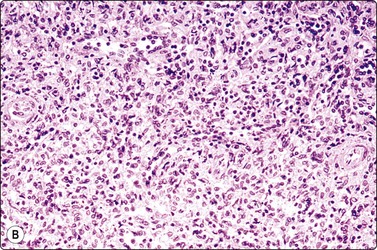

Malignant lymphoma220,222,226,238

The findings in malignant lymphoma in splenic aspirates are the same as in other tissues (see Chapter 5). The abnormal lymphoid cells are more dispersed, distributed as single cells, and tissue fragments are less conspicuous than in smears of non-neoplastic splenic tissue. Non-Hodgkin lymphoma of mixed cell type is particularly difficult to diagnose with confidence in splenic aspirates and immune marker studies by flow cytometry or immunohistochemistry are indispensable.222,249,250 In Hodgkin lymphoma, the diagnosis rests on the demonstration of Reed-Sternberg cells.251